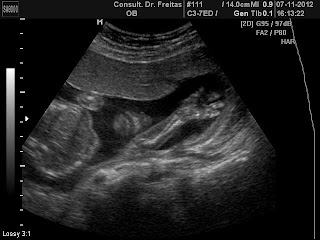

Ultrassom 14 semanas e 1 dia . Ele tava se espreguissando lindo.